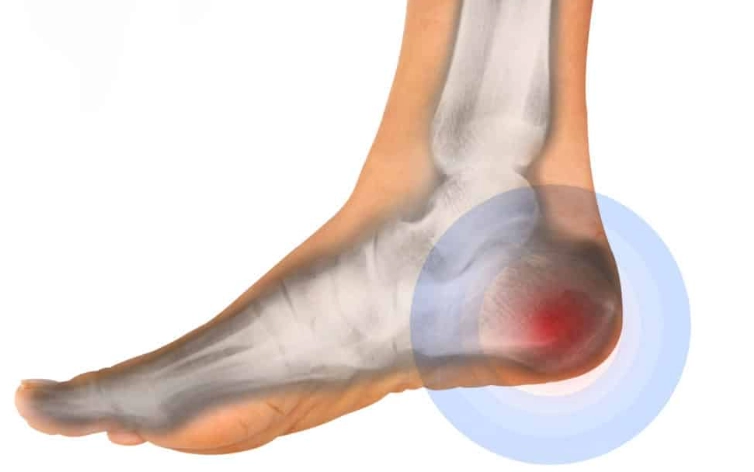

Gãy xương gót (Calcaneal fracture)

16/03/2026

Gãy bong lồi củ xương gót (Calcaneal tuberosity avulsion fracture)